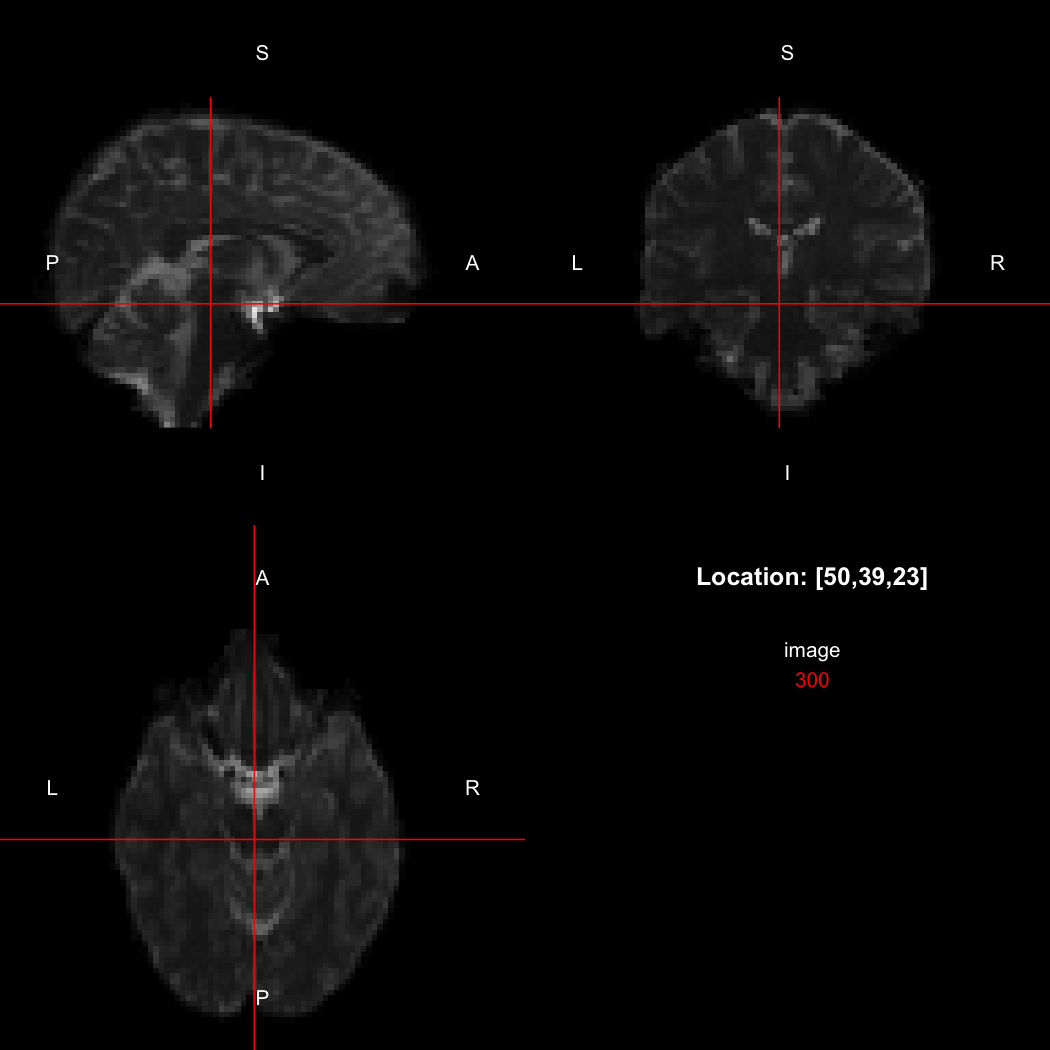

A simple example operation would be to smooth the image with a Gaussian smoothing kernel of standard deviation 4 mm. We can use standard R syntax to perform this operation, return a result, and then show it:

smoothed <- run(smooth_gauss(image, 4))

view(smoothed)

## Setting window to (0, 549.9)

plot of chunk standard

Here, smooth_gauss() requests the smoothing operation, and run() actually runs the pipeline and returns the processed image.

However, the pipe syntax provides an alternative, which can be further simplified because calling view() on a pipeline will implicitly run it.

image %>% smooth_gauss(4) %>% view()

plot of chunk pipe

Notice now smooth_gauss() is now called with only one argument, and view() with none, because the input to the pipe (%>%) is implicitly added first. The benefits to readability of this approach increase substantially as more operations are added to the chain: